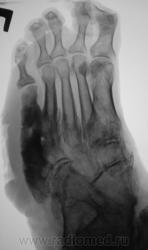

Пациентка направлена на рентгенографию стоп.

Правая стопа.

Возраст - 51 год.

Направительный диагноз - "Диабетическая ангиопатия".

Некоторые коллеги высказали мнение по поводу наличия остеомиелита.

По правой стопе я бы тоже поставил Гарре, но слева такое вылезает. Может все-таки системное?

Хирург, увидев только одну стопу - правую, левая, еще была в работе, ответственно заявил - "остеогенная саркома"...